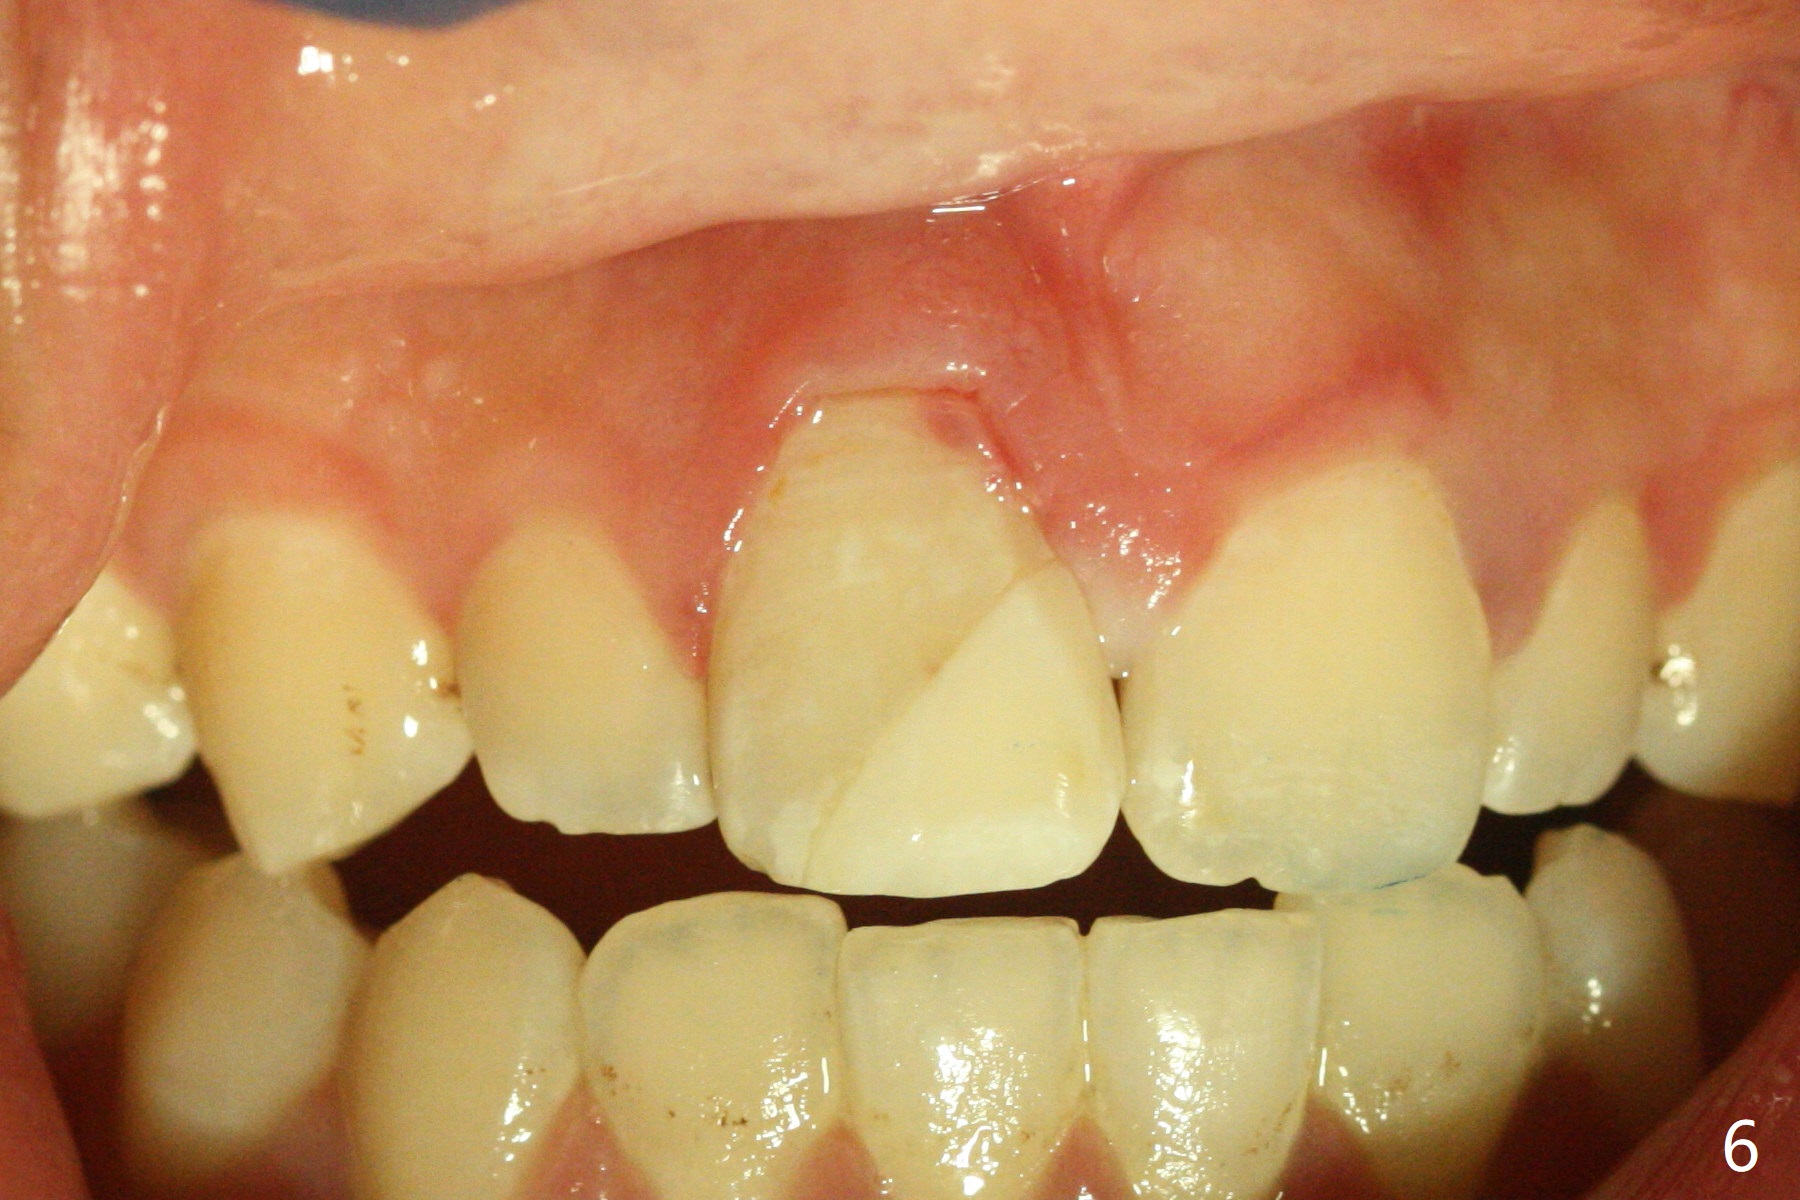

A 16-year-old man fractured the tooth #8 yesterday (Fig.1) with pulpal exposure (Fig.2) and slightly subgingival (Fig.3 <). With 2 gingival retraction cords, rubber dam and floss, the mesial margin is exposed (Fig.4). The mesial pulpal horn is increased slightly with a 330 bur with minimal pulpotomy. MTA is applied (Fig.5 <). A curette is placed over the MTA for hemostasis while it is setting. RelyX Ultimate Adhesive Resin Cement bonding is used to reattach the fracture fragment in place (Fig.6,7). Pulpal vitality will be monitored. A crown will be placed if the tooth discolors due to MTA and the pulp remains vital. Mineral trioxide aggregate (MTA), composed mainly of tricalcic silicate, tricalcic alluminate, bismuth oxide, is a particular endodontic cement. It is made of hydrophilic fine particles that harden in the presence of dampness or blood. The re-attached tooth remains asymptomatic 9 days postop (Fig.8) when he returns for prophy.

16岁男孩,昨天右上中切牙撞击电脑发生折裂(图一),近中牙髓角暴露(图二),裂缘稍微龈下(图三 <),使用两个牙龈牵拉线,橡皮障和牙线,近中折裂边缘暴露(图四)。你会如何处理?使用330钻头稍微扩大髓角开口,去除少量牙髓,填入微量MTA (图五<),希望形成新的牙本质,关闭开口,维持牙髓活性。出血控制后,应用树脂粘合剂将断片固定于原位(图五,六,七)。术后9天牙齿无症状(图八),病人回来洗牙。